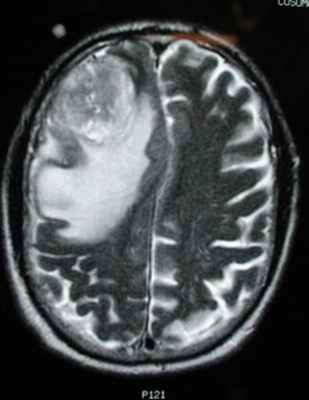

МРТ того же пациента. Т2-взвешенное изображение демонстрирует то же поражение, что и на предыдущем рисунке с заметным отеком и смещением срединных структур. Эти находки соответствуют высокой степени злокачественности опухоли.